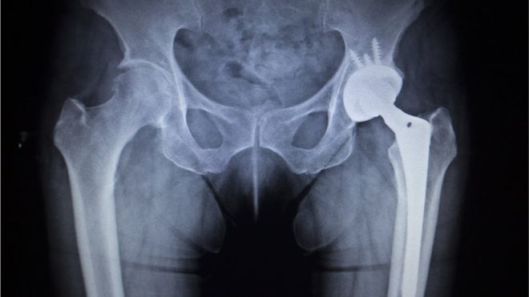

Cost-cutting plans to slash the number of people eligible for hip and knee replacements have been criticised by surgeons.

Three Clinical Commissioning Groups in Worcestershire plan to only treat the most severe cases where pain interferes with daily life and ability to sleep.